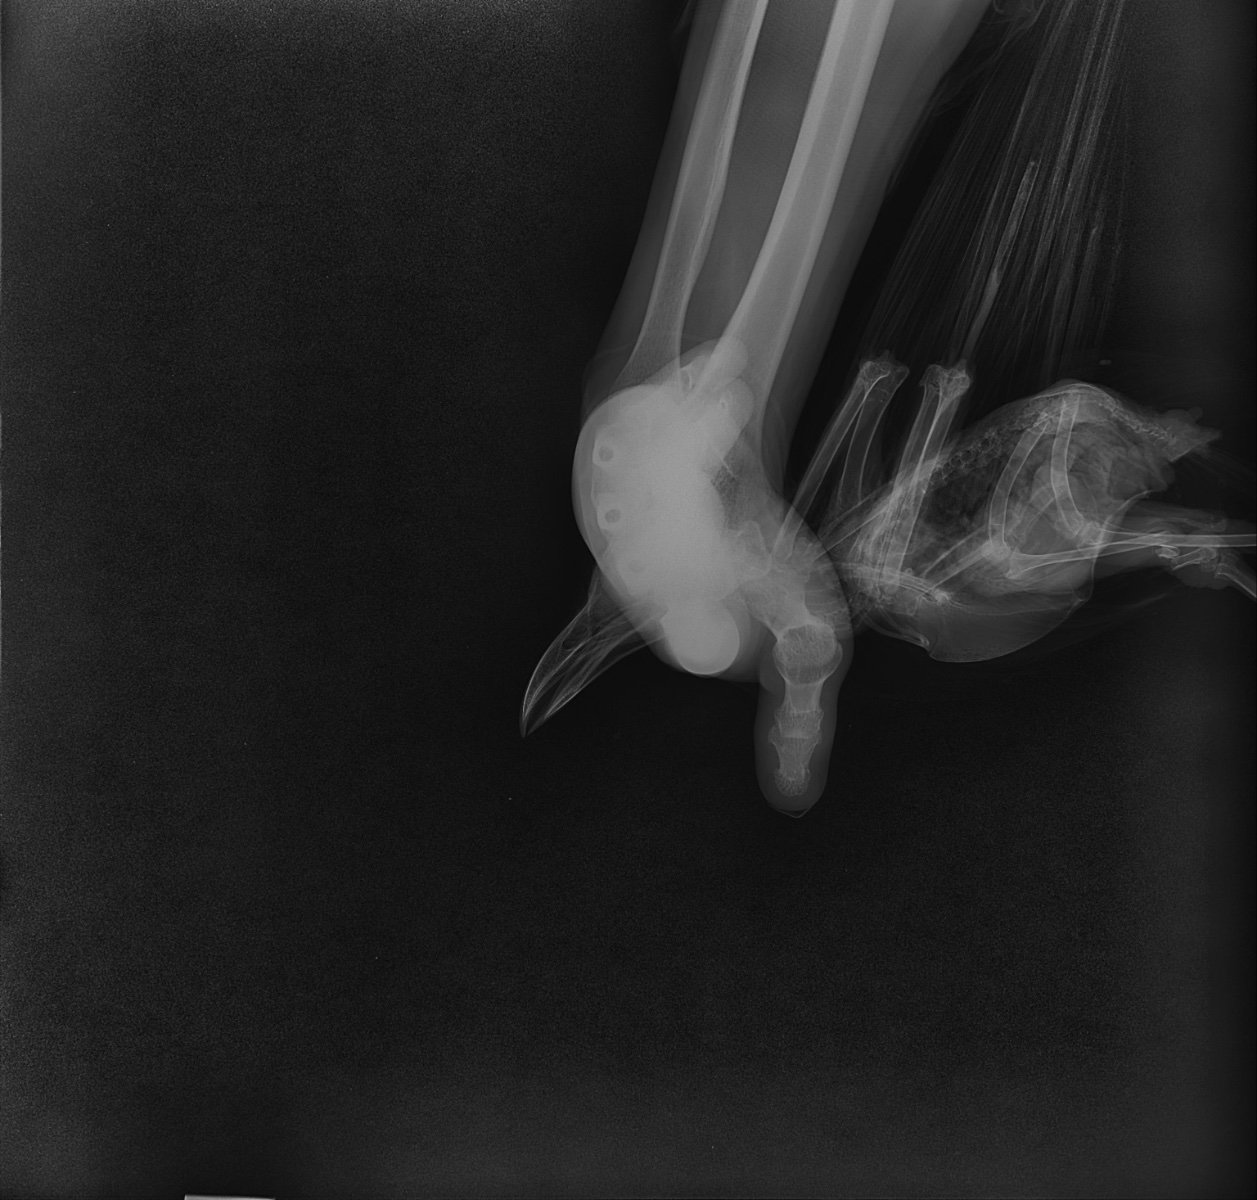

У меня остаются подозрения, что где-то есть открытая рана, личинки не могут быть просто так. По рентгену не вижу, где могла бы быть. Лучше обратиться к Zosia, чтобы посмотрела рентген, быстрее будет по Вацапу в ее профиле.

Пишите @Zosia  на Вотсап +79067739295 , шлите рентген и напишите про мух.